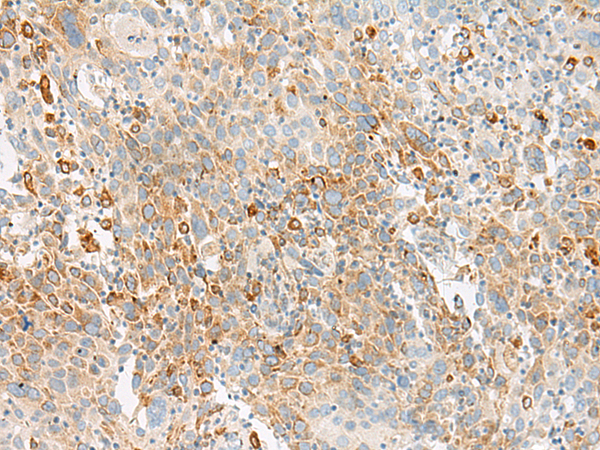

分类: 科研抗体货号: P13480别名: G2A应用: IHC反应种属: Human